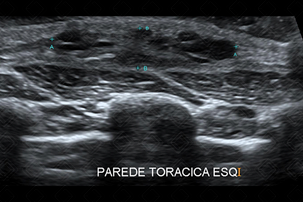

Texto alternativo para a imagem Créditos: Dra. Elazir Mota - Rio de Janeiro/RJ

Descrição das figuras: Formações císticas, com finos septos internos e vascularização periférica ao Doppler colorido, localizada na parede torácica esquerda, compatível com linfangioma.

• Ultrassonografia de partes moles: Trata-se do exame de imagem de escolha para avaliação de malformações vasculares e/ou linfáticas. No linfangioma macrocístico (forma mais comum), a lesão contém formações císticas, de tamanhos variados, com conteúdo líquido e separado por septos hiperecoicos. O interior dos cistos apresenta conteúdo anecoico, exceto quando há sangramento ou processo infeccioso associado, podendo o conteúdo do cisto tornar-se heterogêneo, com nível líquido-líquido. Ao Doppler colorido, a lesão mostra-se avascular (f iguras acima);